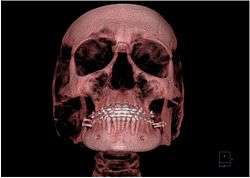

Oral and Maxillofacial Radiology AKA (Dental and Maxillofacial Radiology) is that specialty of Dentistry concerned with performance and interpretation of diagnostic imaging used for examining the craniofacial, dental and adjacent structures.[1] OMFR or DMFR is one of nine dental specialties recognized by the American Dental Association, Royal College of Dentists of Canada, and Royal Australasian College of Dental Surgeons.

Oral and maxillofacial imaging includes, but is not limited to, cone beam CT, multislice CT, MRI, PET, ultrasound scan, dental panoramic radiology, cephalometric imaging, intra-oral imaging (e.g. Bitewing, peri-apical and occlusal radiographs) in addition to special tests like sialographs. Visible light, optical coherence tomography and tera ray imaging are examples of additional methods in use or under development. Image guidance includes Haptic and Robotic devices.